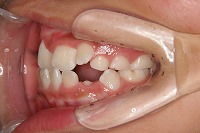

反対咬合を主訴に来院された、右側唇顎裂の10歳6ヵ月の女の子です。診断「右側唇顎口蓋裂で反対咬合を伴う」1期治療で反対咬合の解消と上顎の前歯の並びを修正しました。2期治療は抜歯をせず治療を行いました。